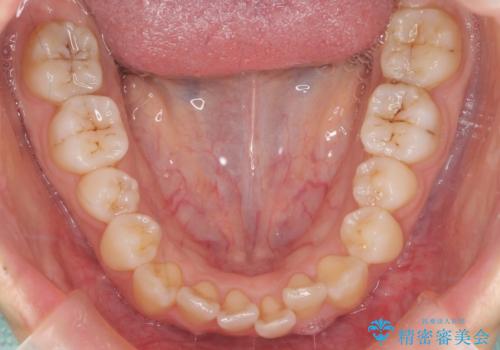

- 八重歯を主訴に来院。

右下5番が神経のない歯で、さらに違和感があったため、抜歯をして矯正しました。

通常は4番を抜くのが矯正治療には一番都合が良いのですが、健全歯を残して治療しています。

抜歯ケースで八重歯でしたが、1年半で治療を終えることができました。